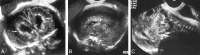

Background and purpose: Congenital cytomegalovirus (CMV) infection can cause a wide range of brain anomalies. These changes have been well described postnatally, but descriptions of their in utero evolution are scarce. The purpose of this study was to analyze the sonographic spectrum of intracranial abnormalities in fetuses with proved CMV infection and to determine characteristic patterns of this infection.

Methods: We reviewed the transabdominal and transvaginal sonograms of eight fetuses with proved CMV infection. The sonographic analysis searched for signs of ventriculitis, leukomalacia, calcification, vasculitis, and periventricular cyst formation. The gyral pattern, corpus callosum, and cerebellar morphology also were examined. Fetal MR imaging was performed in two cases.

Results: The sonographic diagnosis of suspected CMV infection was made at a mean gestational age of 27.5 weeks (range, 22-37 weeks). An abnormal pattern of periventricular echogenicity was found in all fetuses. Echogenic intraparenchymal foci and ventriculomegaly were present in five fetuses. Other signs of fetal infection were intraventricular adhesions, periventricular pseudocysts, sulcation and gyral abnormal patterns, hypoplastic corpus callosum, cerebellar and cisterna magna abnormalities, and signs of striatal artery vasculopathy. For all fetuses, transvaginal sonography provided additional information. Fetal MR imaging provided additional information in one case.

Conclusion: The presence of the described sonographic findings, particularly if two or more are present in the same fetus, is an indication for CMV investigation.